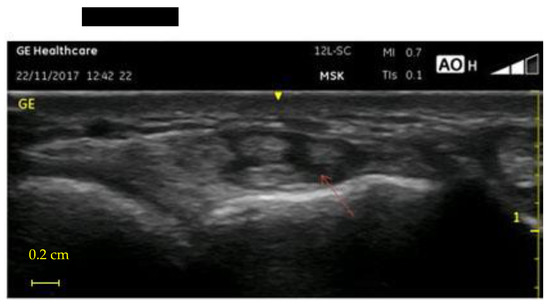

- UI of the hand-wrist area, performed with portable ultrasound device (Venue Scan, Venue 40, GE Healthcare®, Chicago, IL, USA) that allowed the researchers to store the examinations for further evaluation and discussion with other hospital experts in the final evaluation of all cases. A trained sonographer performed the wrist ultrasound. According to the European Society of Musculoskeletal Radiology’s protocol (ESSR) [23], acoustic windows were investigated in both the dorsal wrist, focusing on the extensor tendons and the radiocarpal joint, and the ventral wrist, focusing on the flexor tendons and the median nerve (Table 1).